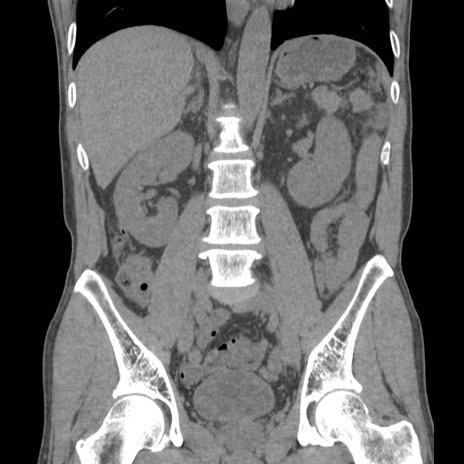

症例56 CT(冠状断像)

脂肪ウインドウ